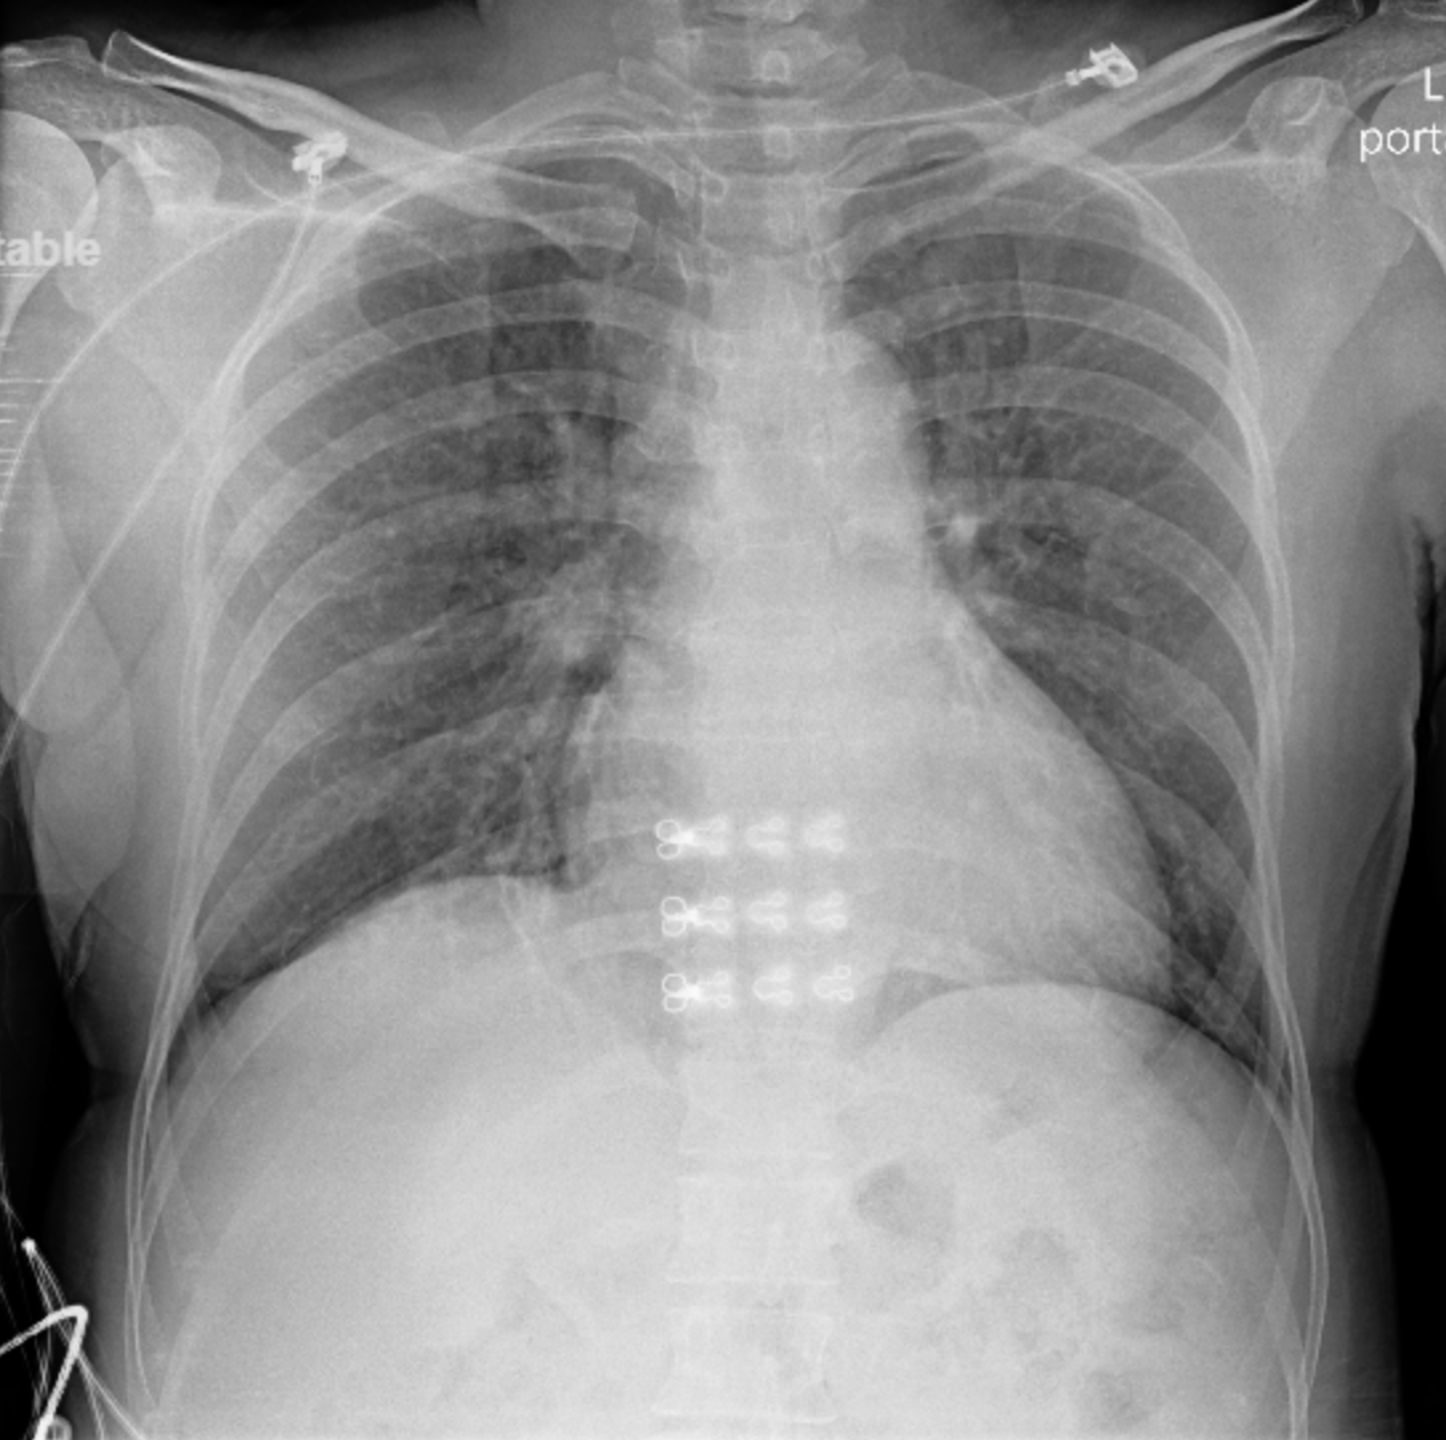

Initial electrocardiogram demonstrated diffuse ST-segment depression with ST-elevation in leads aVR and V1. The patient subsequently developed ventricular fibrillation requiring immediate cardiopulmonary resuscitation and defibrillation. During emergency transfer to the cardiac catheterization laboratory, she experienced recurrent ventricular fibrillation and profound cardiogenic shock.